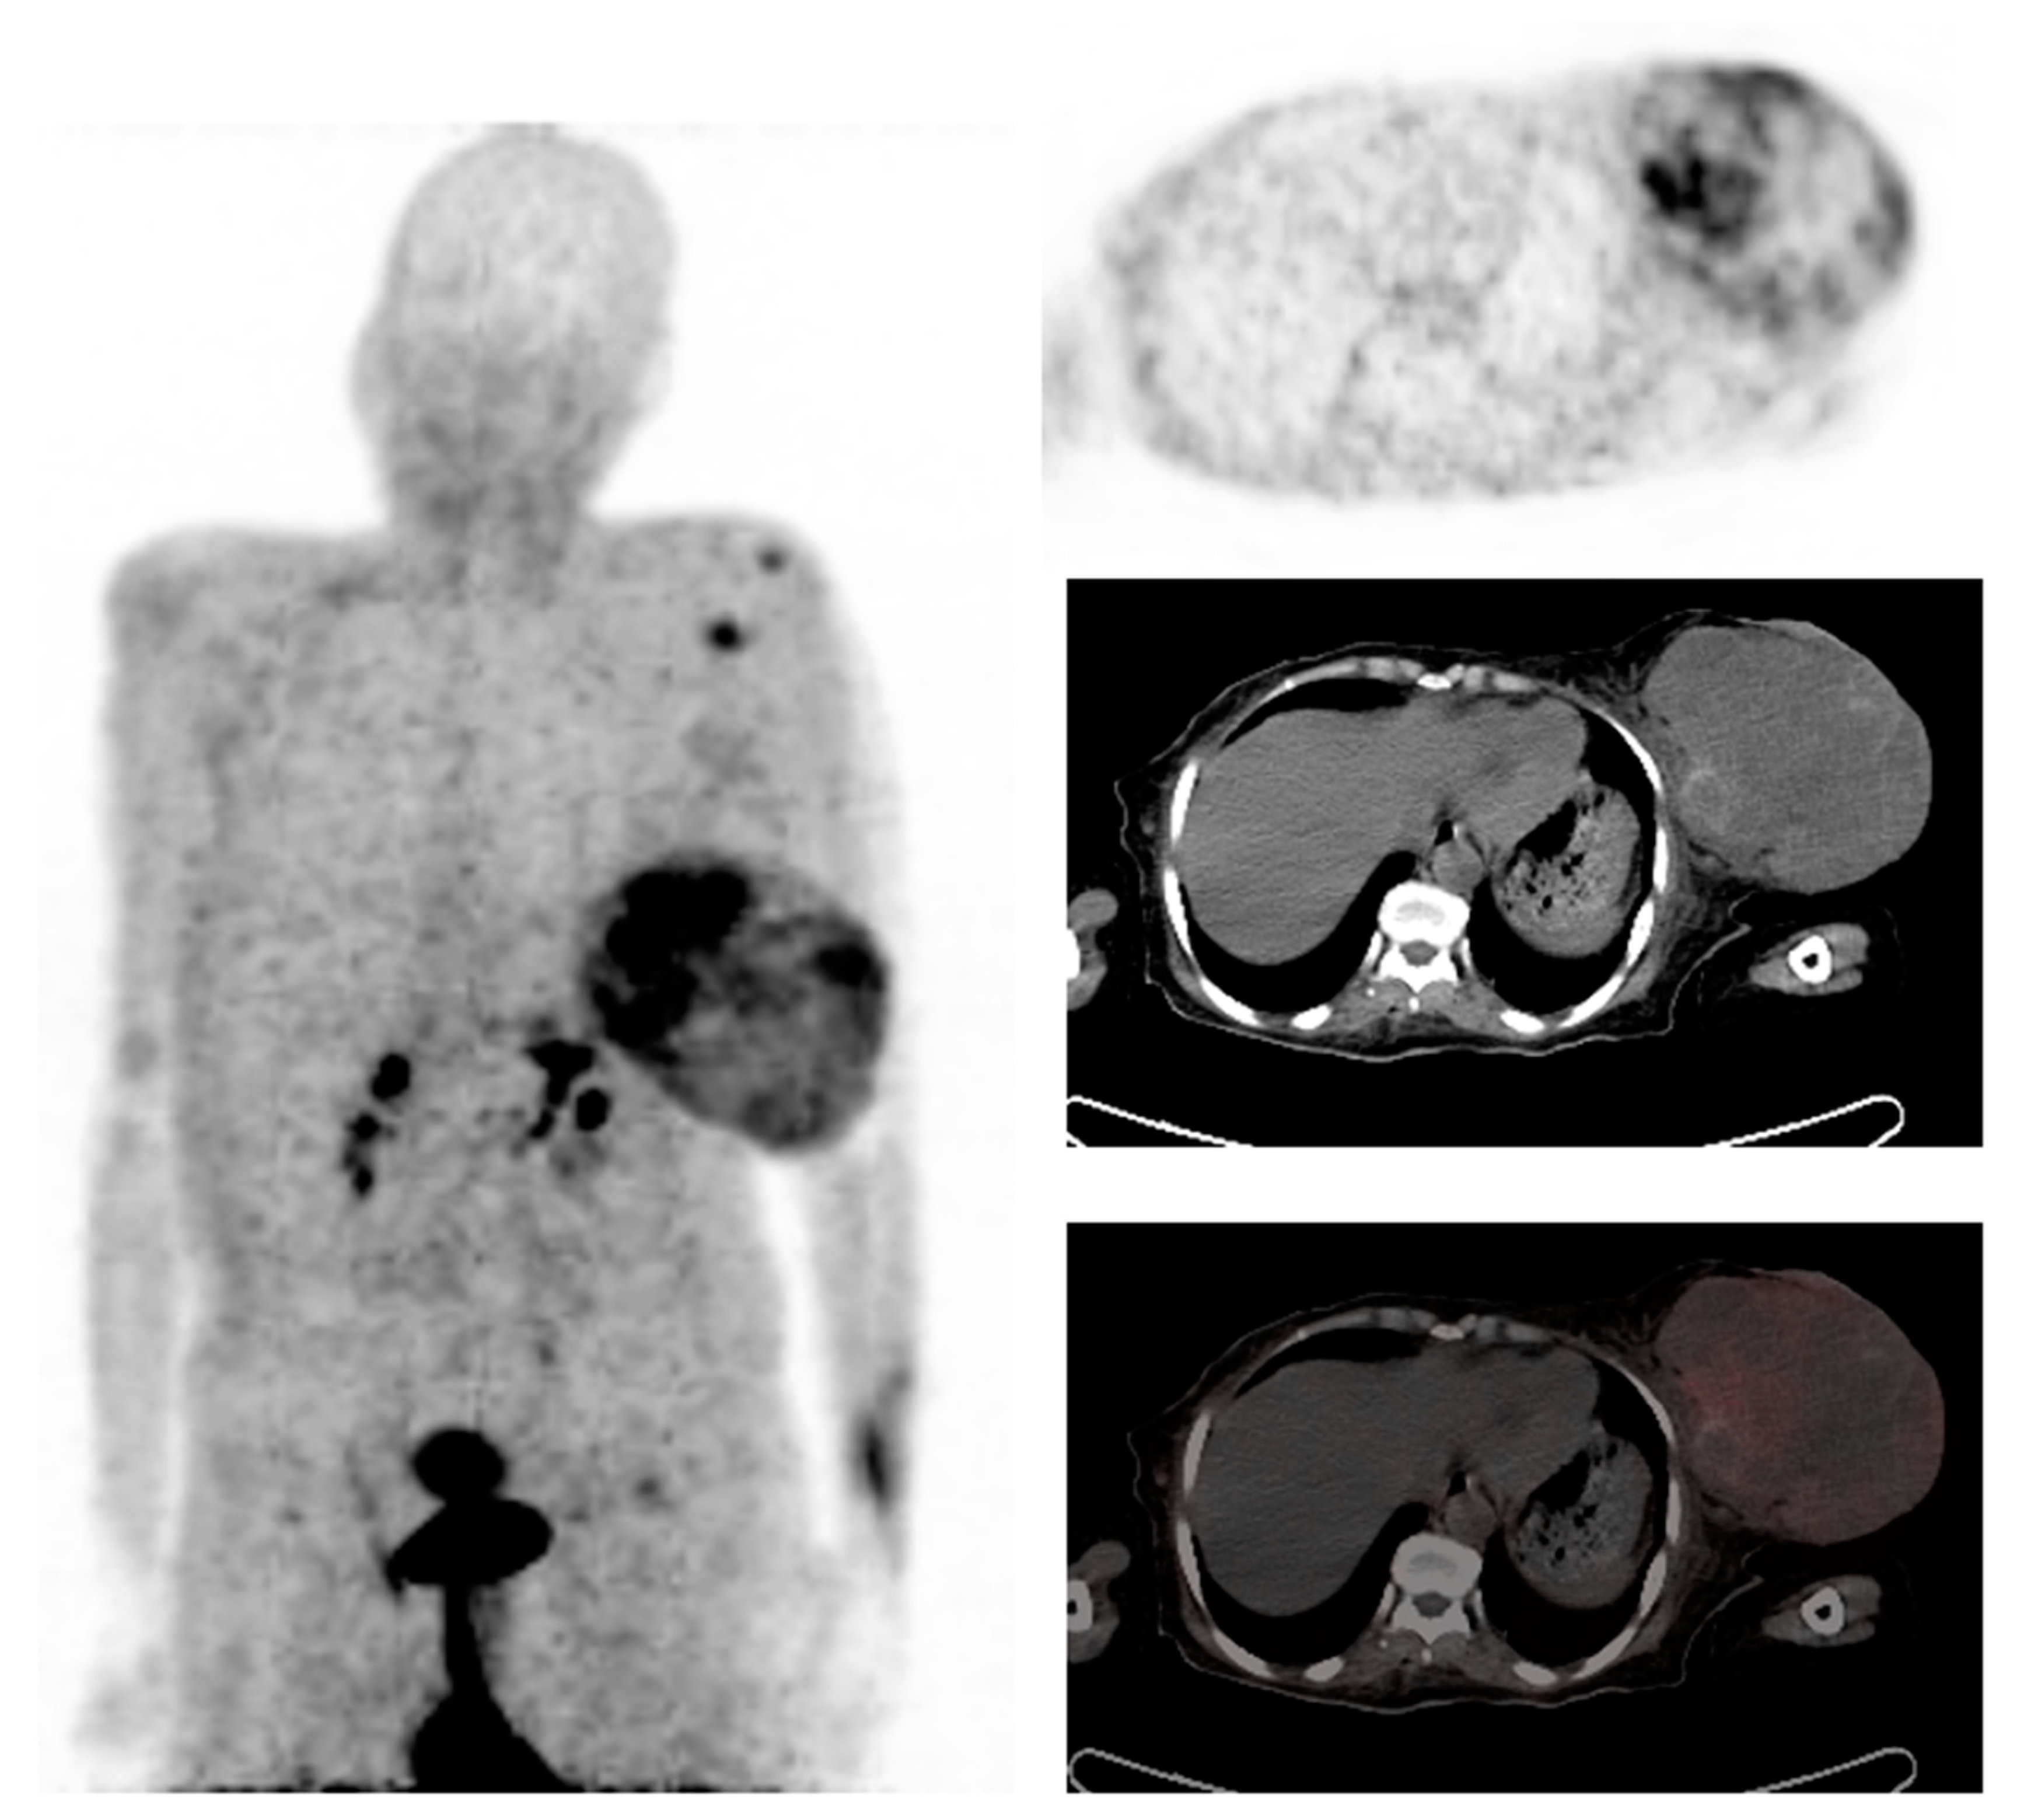

3.1. Fibroblast Activation Protein

4.1. FAPI